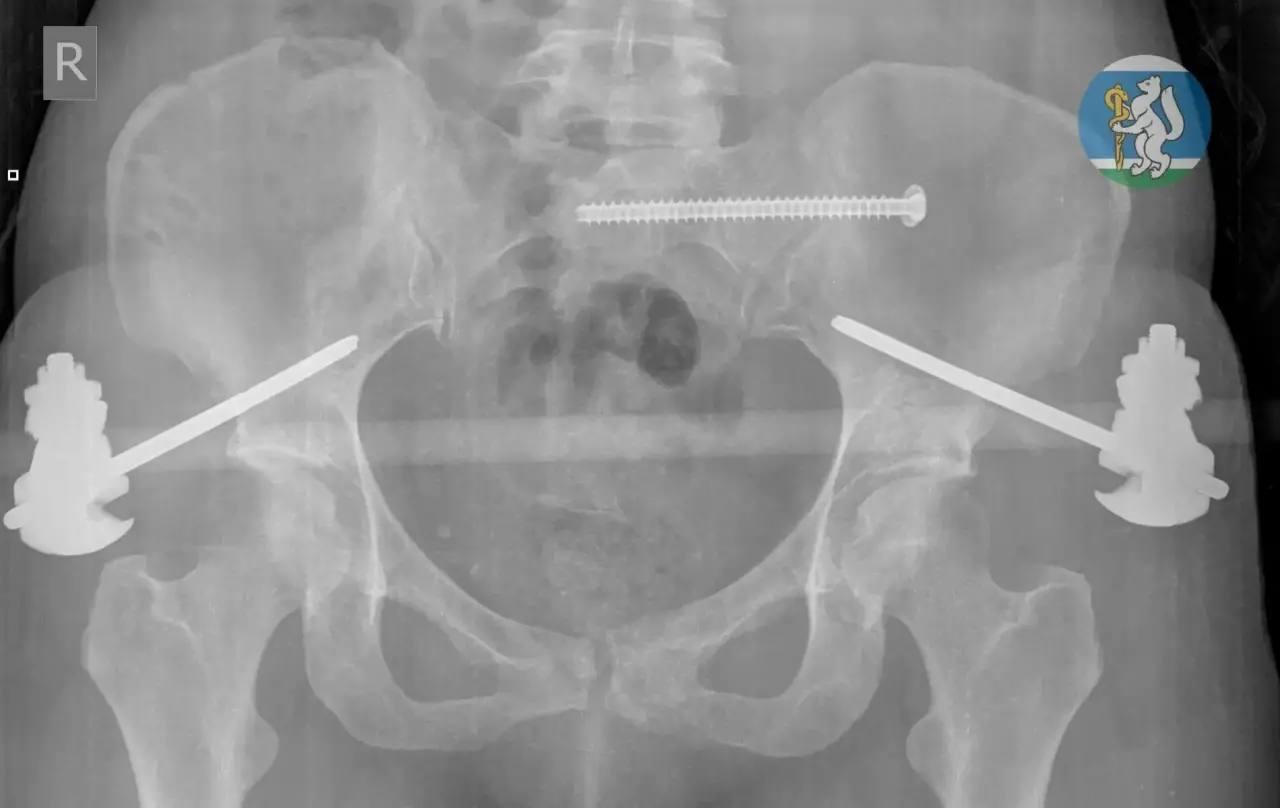

У пострадавшей диагностировали множественные переломы таза и другие критические травмы

В городскую больницу №36 пострадавшую доставили в состоянии тяжелейшего травматического шока. Обследование выявило у нее черепно-мозговую травму, повреждение позвоночника, множественные переломы таза и открытые переломы ноги. Как отмечают врачи, большинство пациентов с такими повреждениями не доживают даже до прибытия в медучреждение.

После экстренной операции женщина находилась на искусственной вентиляции легких в реанимационном отделении. Через полторы недели её перевели в травматологию, а спустя ещё две недели медики успешно провели операцию по частичному демонтажу аппаратов внешней фиксации и синтезу сломанных костей.